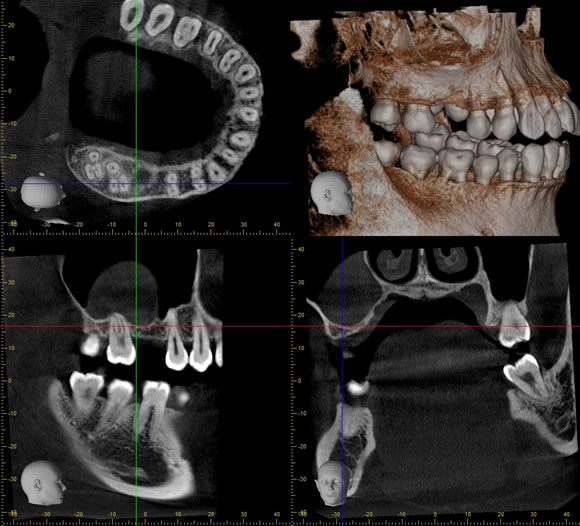

歯牙腫摘出 症例2+埋伏歯(まいふくし)

歯牙腫摘出と埋伏歯抜歯のコンビネーション症例です。お口の違和感で来院された20代女性の方です。抜歯、摘出はピエゾサージェリーを併用するので周囲の歯にダメージを与えず摘出可能、低侵襲に行えます。

通院回数事前検査から手術~抜糸~消毒などを含めて5回、治療期間は約1ヶ月でした。静脈内鎮静法による無痛リラクゼーション麻酔を行い、無痛下で行いました。

料金

静脈内鎮静法による麻酔代込み:約15~20万円(保険適用外)